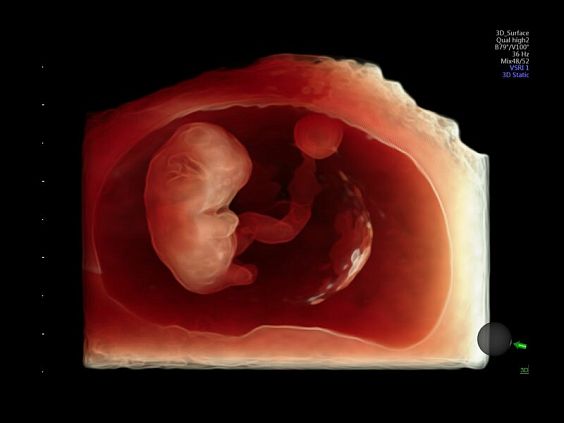

• Программа объемной визуализации плода классический HD-Live + расширенный пакет Hdlive Silhouette и Studio:

• HDlive Silhouette - режим "Силуэт" с подчеркиванием границ тканей и объектов, "объем в объеме"

• HDlive Studio - три независимых источника освещения с регулировкой интенсивности

Инновационная технология визуализации HDlive обеспечивает получение реалистических изображений за счет эффекта объемного зрения, повышая достоверность клинической оценки. Теперь режим HDlive дополняют две новые функции:

• Технология HDlive Silhouette — задает разный уровень прозрачности, помогая выявлять контуры внутренних структур и точнее оценивать состояние плода в первом триместре.